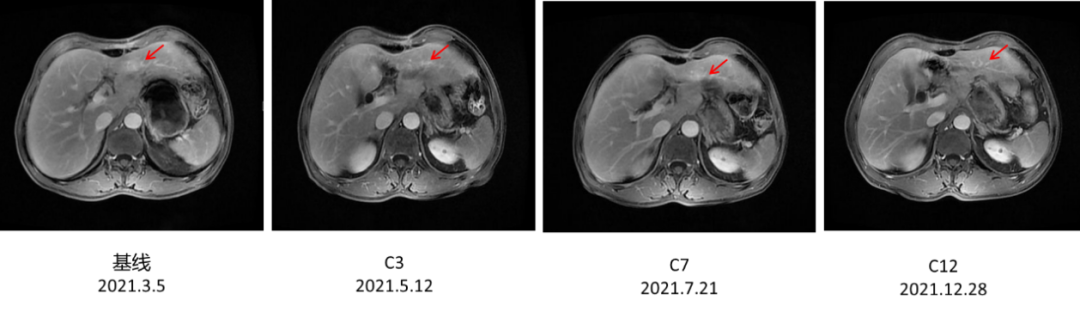

2021年5月12日、7月21日和12月28日:上腹部MRI示:肝、胃术后改变,肝左叶环形强化影,体积较前逐渐减小(最大径分别为15.8mm、14.8mm、10.6mm)。(图5)

图5.上腹部MRI

汉曲优®Ⅲ期临床研究[3]结果显示,汉曲优®与原研曲妥珠单抗疗效等效,安全性、免疫原性相似,曲妥珠单抗生物类似药得到NCCN-GI指南、CSCO-GI指南的用药推荐,2020年《中国生物类似药专家共识》也指出:生物类似药与参照药疗效等同、安全性相似,临床上可以替代使用。在本病例中,患者综合经济因素等原因,在使用原研曲妥珠单抗7周期有效后,转换为曲妥珠单抗生物类似药(汉曲优®)继续治疗,目前已使用10周期,并于2021年12月28日复查上腹部MRI示:肝、胃术后改变,肝左叶环形强化影,体积较前逐渐减小,达到PR,显示出良好的疗效和安全性。